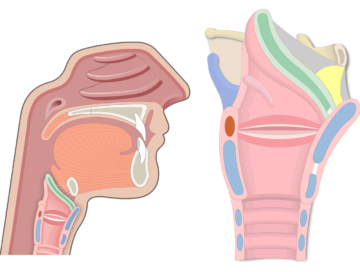

Pharynx

Throat

Oropharynx

Space behind the mouth

Larynx

Voice box; located just above trachea and esophagus